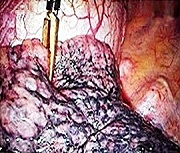

従来の肺がんの手術は20cm前後の皮膚切開で肋骨、筋肉を切断し、肋間を開胸器で開大しなければなりませんでした(開胸手術)。当院では内視鏡を用いた手術(胸腔鏡手術)を行っており、従来の手術法と比べて傷が小さく筋肉や肋骨を切断しないため、術後の 痛みや機能の悪化が少ないと考えられています。当院では高度の進行病変などを除いては、ほぼ全例に胸腔鏡を用いた手術を行っております。